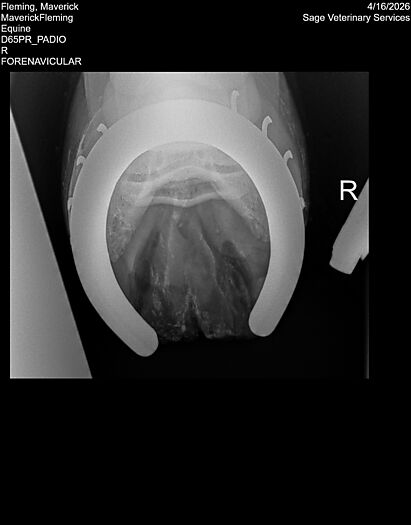

**Maverick sells at the Colorado Horse Sale’s Best of the West Select Sale on May 30th in Castle Rock, CO - He will complete the riding & handling Sift Exam, baseline veterinary exam, and will sell with 4 total radiographs (DLPMO & Front Foot Lateral)**